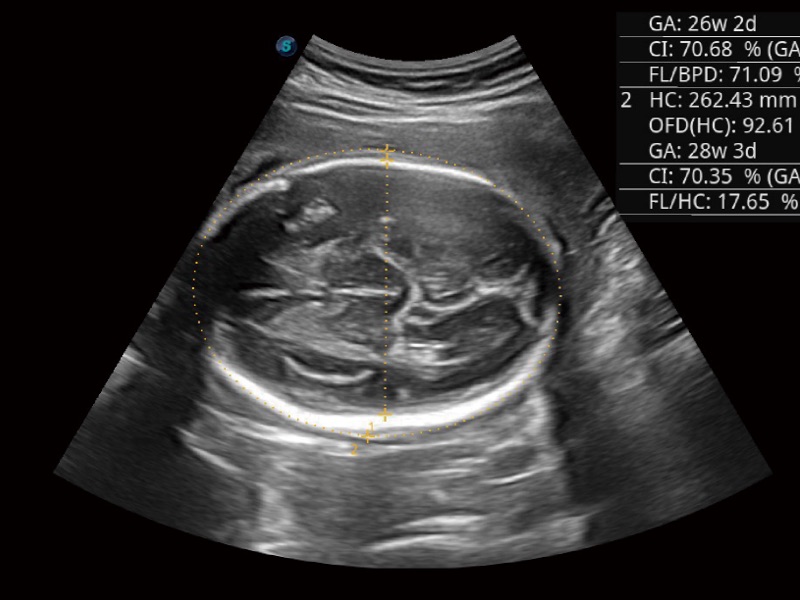

妇产科应用

三维光影成像技术采用新型的渲染方式,增强边缘信息,使得轮显示清晰完整,为临床提供丰富、直观的三维结构,提供临床诊断准确性。

超声检查得益于实时性、经济性、便捷性,目前广泛的应用于临床工作中,超声检查设备已成为帮助临床医生轻松地完成诊断工作的好伙伴。P20 Plus集成了一整套包含了腹部、心血管、小器官、妇产科等全面临床应用功能,轻松应对各种临床问题。